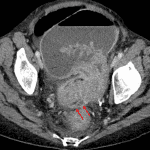

- Marked diffuse colonic distension measuring up to 9 cm in diameter with transition to normal caliber in the distal sigmoid colon where there is marked circumferential mural thickening

- Fistulous tract along the posterior margin of the distal sigmoid colon extending inferiorly toward the vaginal apex

- Locules of gas along the right anterior aspect of the urinary bladder with circumferential bladder wall thickening

- Large bowel obstruction (colonic stricture)

Findings concerning for large bowel obstruction with transition point in the sigmoid colon where there is circumferential mural thickening. Primary differential considerations are neoplasm and postinfectious/postinflammatory stricture. Recommend surgical evaluation.

Possible colovaginal fistula. This could be further evaluated with a CT pelvis with rectal contrast.

Small amount of gas along the anterior right aspect of the urinary bladder which may relate to emphysematous cystitis, colovesical fistula, or could be secondary to recent instrumentation.